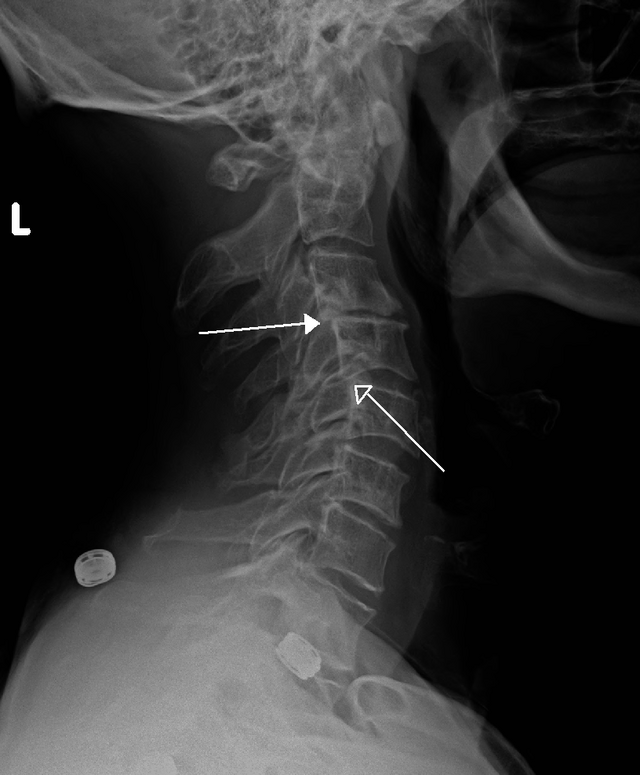

La combinación de ambos procesos que ocurren simultáneamente en muchos pacientes se conoce como espondiloartrosis. Figura 3 Muchas veces estos términos se emplean como sinónimos.

Figura 3. Espondiloartrosis. Rx lateral de columna lumbar con enfermedad discovertebral con osteofitos (flecha), discopatias con disminución del espacio discovertebral (flechas discontinuas) y afectación de elementos posteriores (artrosis facetaria)

Fuente: ver aquí